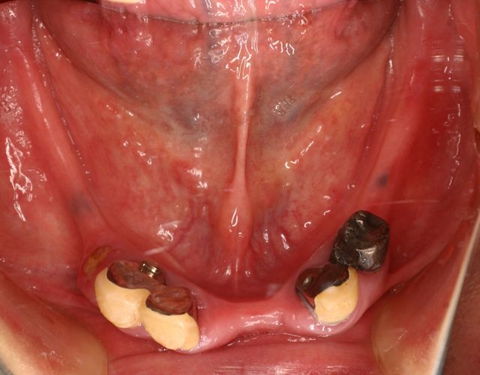

術前(下顎粘膜面、鏡像)